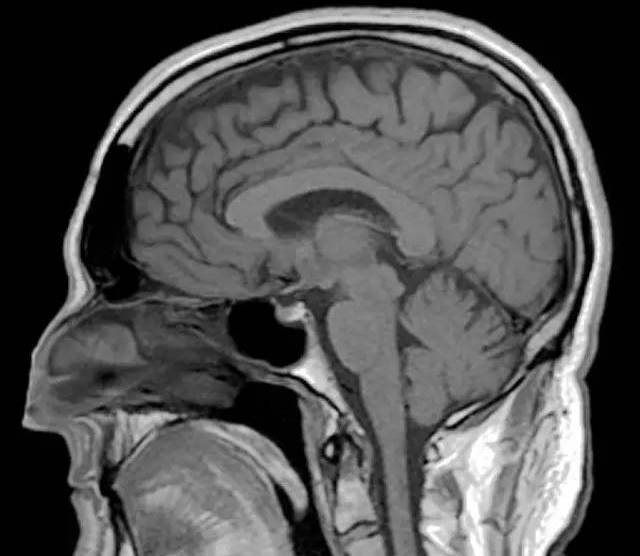

这场脑炎让Clive的海马体受到了永久损伤,而海马体又是将短期记忆传递成长期记忆的重要器官,这导致了这位曾几何时的天才音乐家的大脑,彻底丧失了长久记忆的功能。

医生说,因为人类的大脑在记忆音乐时,是用的程序记忆Procedural memory,这是一种长期记忆,也叫做内隐记忆的形式。反复弹奏钢琴的身体动作,能够触发人的内隐记忆,这也是为什么Clive能够记得音乐的原因。